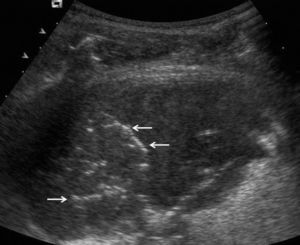

En pacientes de difícil movilización, como los ingresados en unidades de cuidados intensivos, la ecografía también es útil para determinar si las alteraciones visibles en la radiografía anteroposterior en decúbito supino corresponden a derrame pleural o a consolidaciones parenquimatosas (fig. 2). Además, como se comenta más adelante, también permite la obtención de líquido pleural de forma rápida y segura.